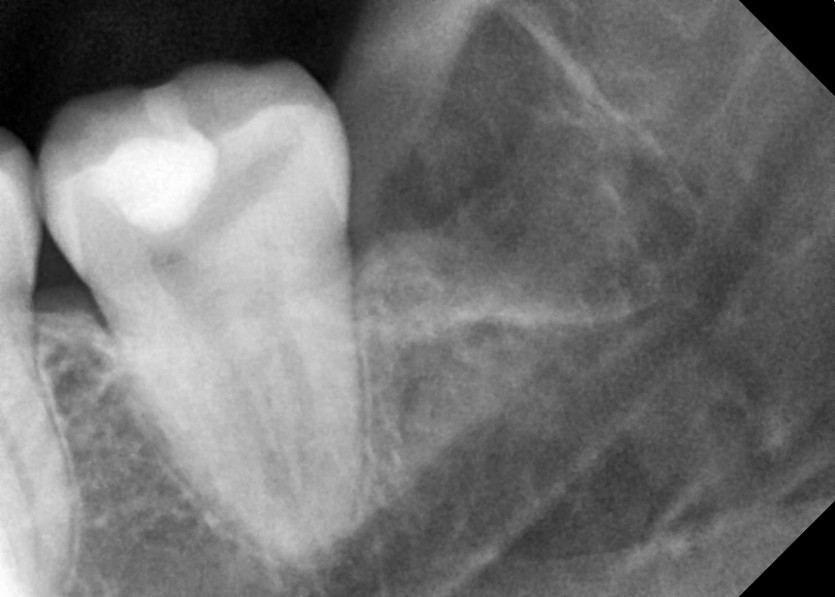

#18,28,38,48 사랑니 발치

구강 외과 전문의가 당일 발치했습니다.